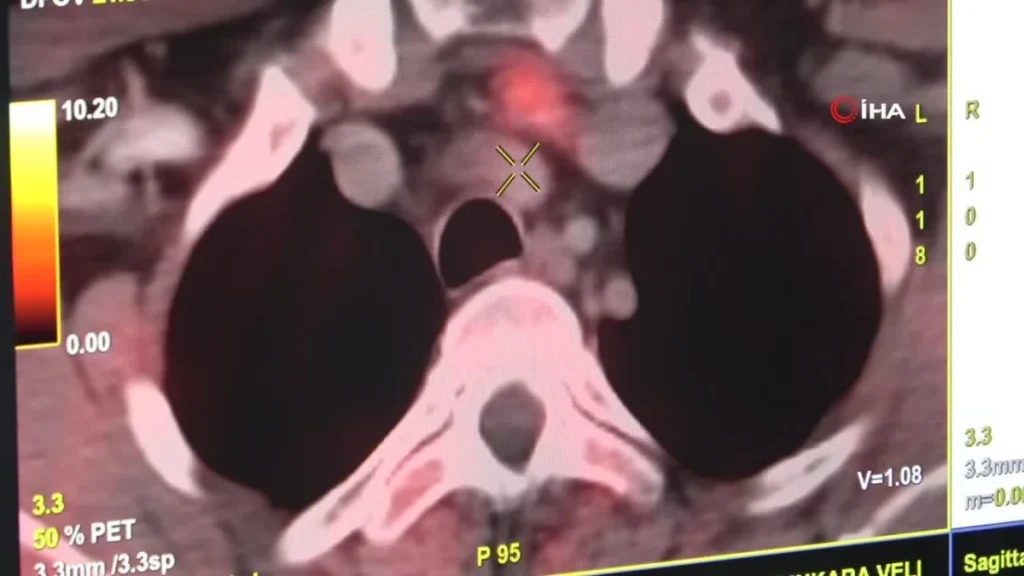

Doç. Dr. Kömek, “İlk olarak prostat kanserlerinde kullanılan bir görüntüleme sistemi olan Kolin PET, rastlantısal yapıtı uzunluğunda tutulmasıyla ve o bölgede paratiroid çıkmasıyla kullanılmaya başlandı. Sensitif ve spesifik pahaları epey yüksek, bilhassa öbür formüllerle bulunamayan lezyonlarda yüksek saptama oranlarına sahip. Bu prosedürle enjeksiyondan 5 dakikadan itibaren manzara alınabiliyor. Kolin PET, PET BT görüntülemelerinde kullanılan bir formül. 5’inci dakika ile 60’ıncı dakikadan sonra imgeler alınarak daha evvelce lokalizasyonunu saptayamadığımız paratiroid adenomlarının lokalizasyon saptamışında kullanılan bir yöntem” tabirlerine yer verdi.